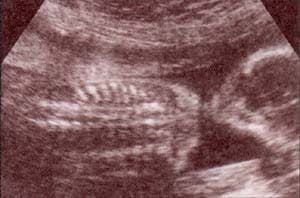

fig 26. – (a).reja costal. |

fig. 26 – (b).ay b. cortes tangenciales y frontales a las 21 semanas |